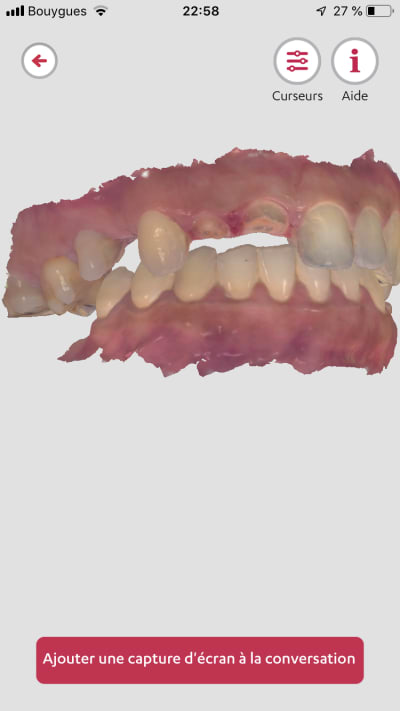

Exemple de ce sue sort une trios 2 de 2013..

Un exemple de scan avec matching emp pour richmond tenon anatomique sous stellite.

> Pas mal pour une vielle dame ! ?

> Les zones proximales entre 6 et 7 ..

Ces images proviennent de quelle camera ?

Trios 2 couleur de 2013...